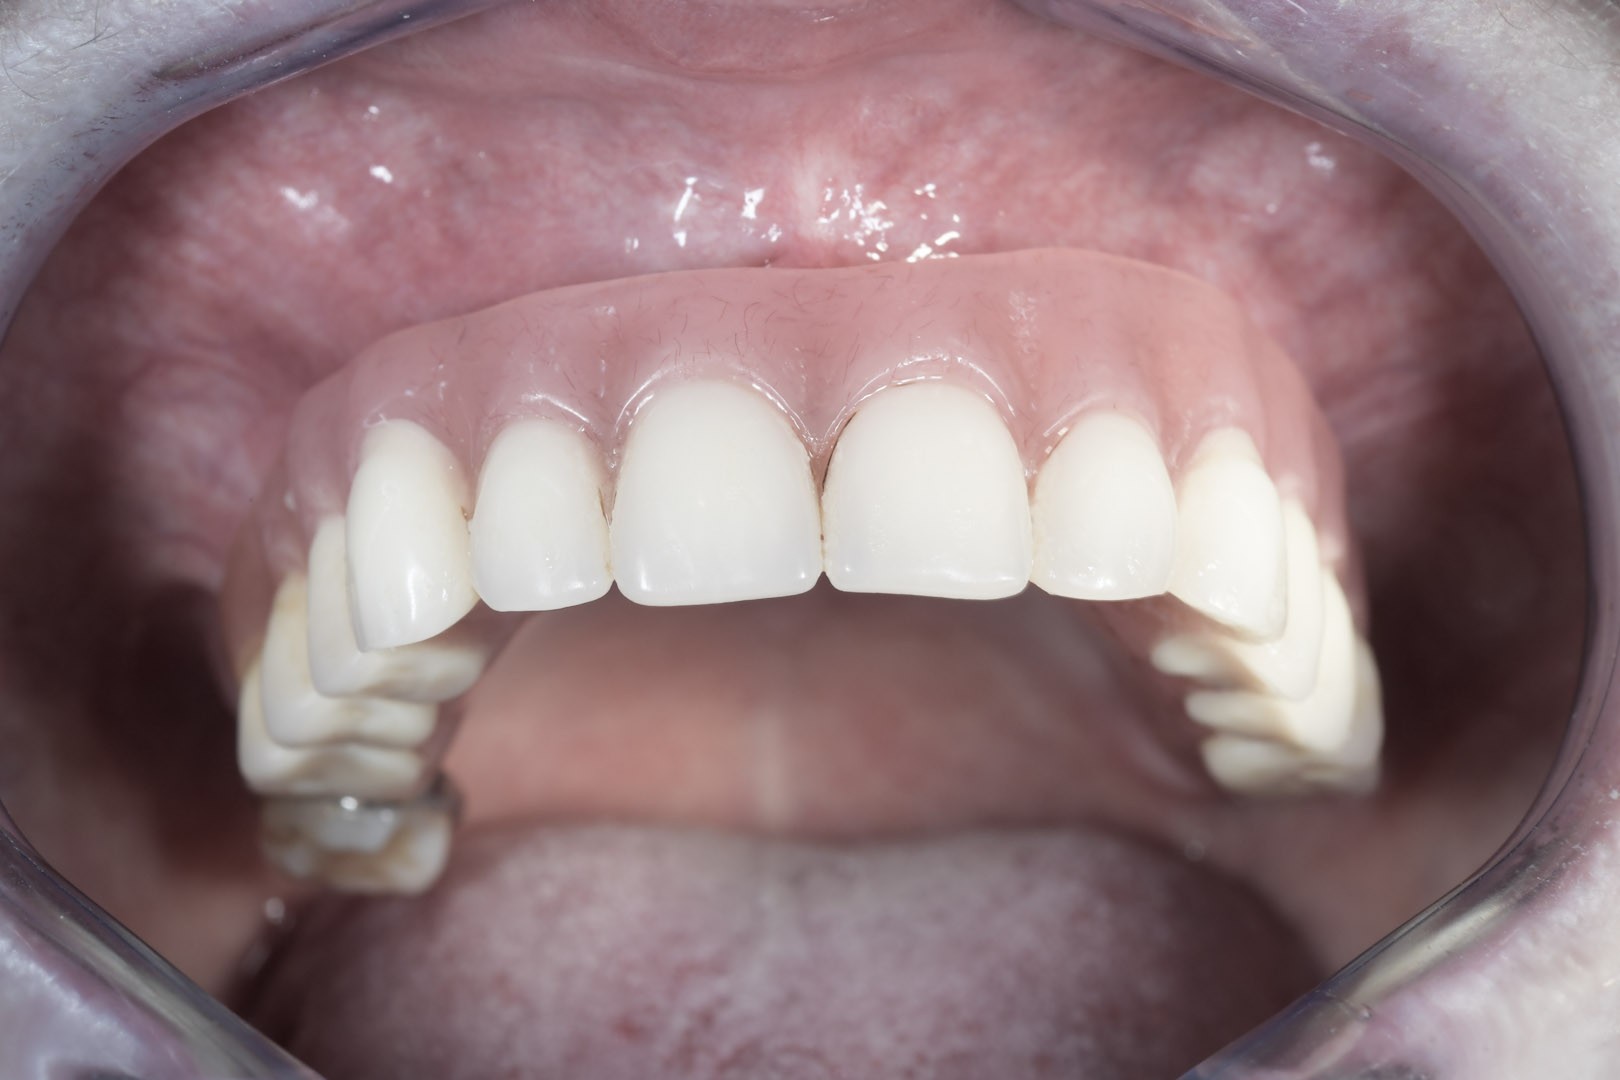

Przy bezzębiu zawsze istnieje możliwość wykonania uzupełnień protetycznych bez zastosowania implantów i są to całkowite protezy osiadające. W zależności od stanu kości szczęk i żuchwy można wykonać protezy lub mosty mocowane na implantach. Mocowanie protez na implantach może być rozłączne, jak w przypadku protez Overdenture, zwanych również nakładowymi. Oznacza to, że proteza w każdej chwili może być odczepiona od platform implantów przez pacjenta i wyjęta z jamy ustnej. Najbardziej jednak pożądane przez pacjentów rozwiązania protetyczne przy bezzębiu to stabilne, niezdejmowalne mosty, które cementuje się lub przykręca na stałe do implantów. One najlepiej imitują estetykę i funkcję naturalnego uzębienia.

W zależności od stadium zaniku kostnego mamy różne możliwości implantacji oraz odbudowy kostnej. W ślad za możliwościami implantologicznymi idą rozwiązania protetyczne mniej lub bardziej komfortowe dla pacjenta. Za komfortowe, tym samym optymalne, uznaje się te, które są na stałe montowane na implantach. O możliwości ich zastosowania decyduje rodzaj zastosowanych implantów, ich ilość i rozmiary, siła, z jaką są posadowione w kości, jakość, wymiary oraz fakt, czy była odbudowywana czy tego nie wymagała.

Jest to technika rekonstrukcji protetycznej – odbudowy uzębienia na implantach, której dokonuje się w dniu zabiegu operacyjnego ich wszczepienia. Warunkami koniecznymi do spełnienia i zagwarantowania poprawności tej metody są prawidłowa stabilizacja implantów oraz właściwie stworzony plan leczenia w oparciu o diagnostykę obrazową podłoża kostnego. Bywa, że w technice tej pomocna jest cyfrowa nawigacja, która dzięki szablonom chirurgicznym, wykonanym na miarę konkretnego pacjenta, umożliwia idealne pozycjonowanie implantów w kości – przez to, że planowane przed zabiegiem .